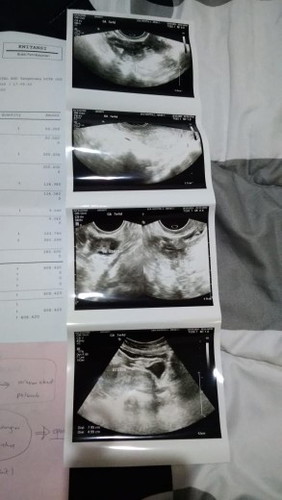

Baca lagi2 Februari 2019 aku keguguran di usia kandungan 5minggu. Alhamdulillah tanpa di kuret, pas usg rahim bersih tdk ada jaringan yg tertinggal. Sekitar 3bulan pemulihan sambil tunggu siklus haid normal lgi, bulan juli 2019 alhamdulillah positif hamil lagi skrng usia kandungan ku udah 36minggu. Saran ku, setelah keguguran bunda langsung minum vitamin asam folat, dan tunggu siklus haid normal jangan lupa catat setiap tanggal haid ya.